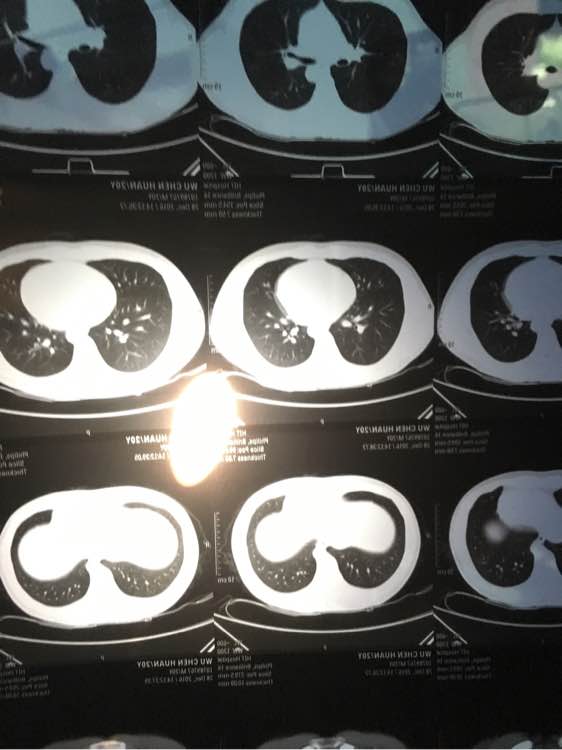

做了个肺部CT,请专业人士看看,谢谢啦